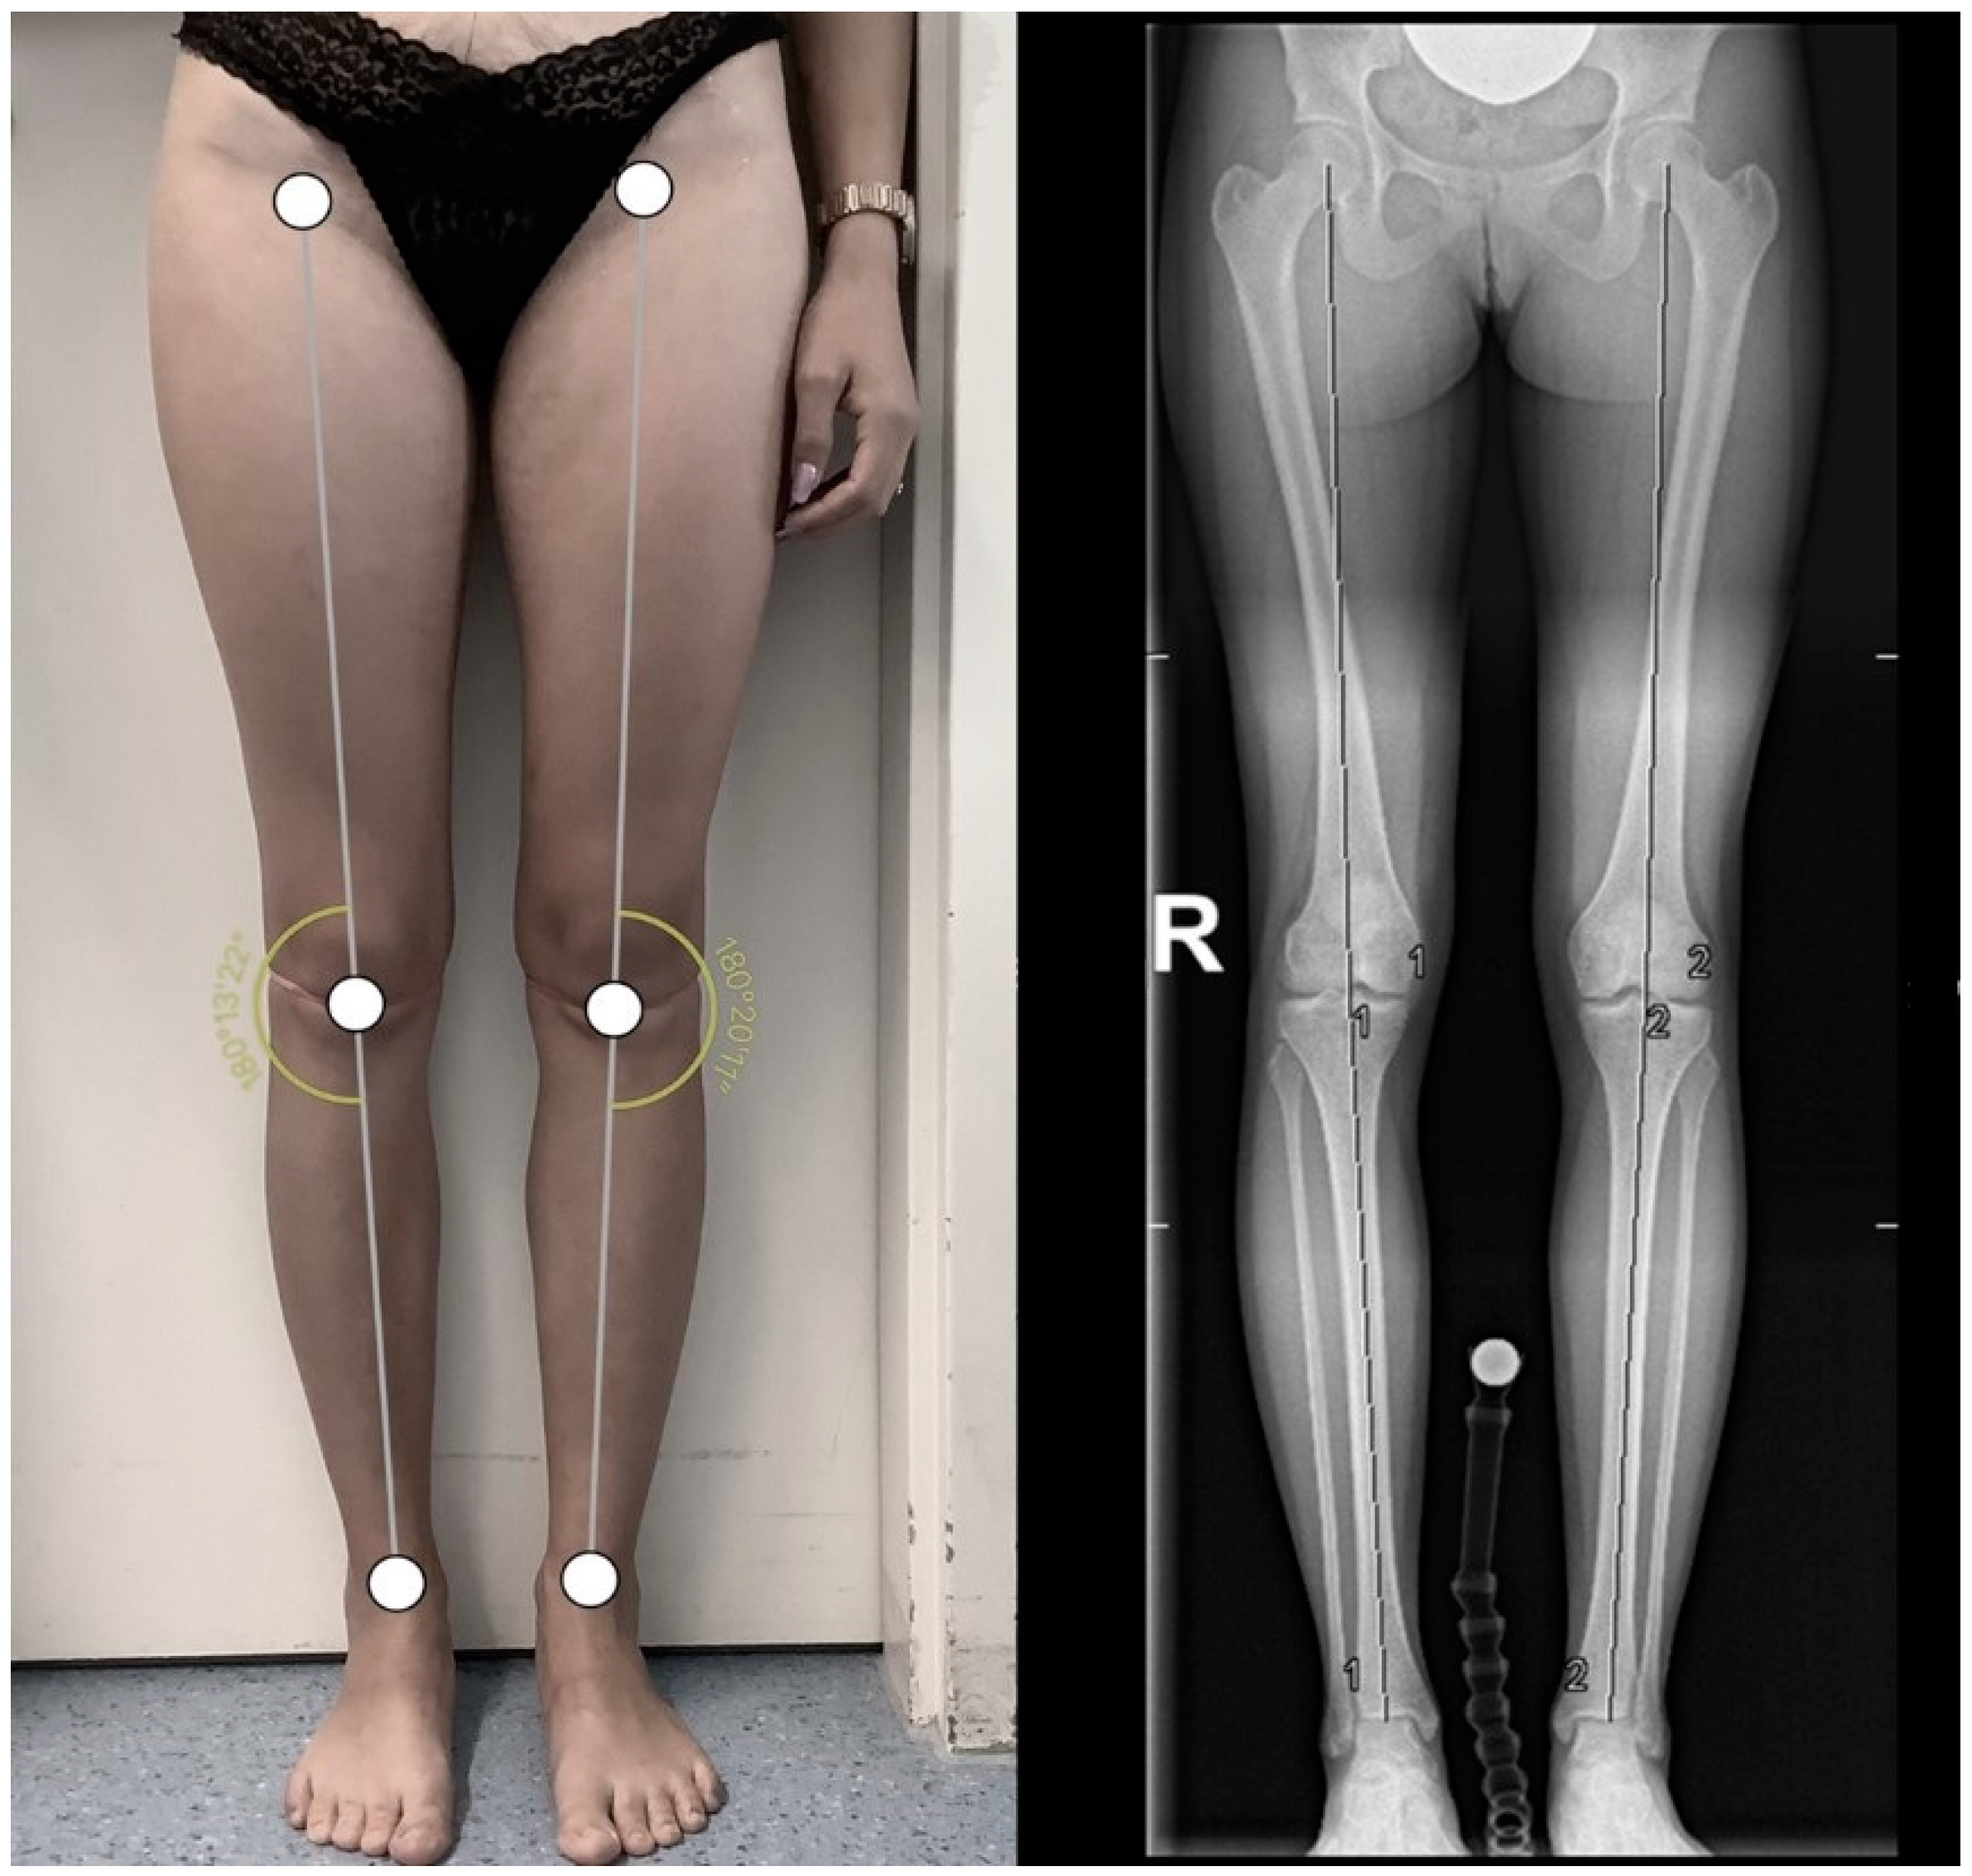

Preliminary Results of Measurements of Frontal Plane Knee Alignment Using a Standardized, Sonographic-Assisted Digital Photograph—A Reliable and Accurate Alternative to a Full-Leg Radiograph?

2. Materials and Methods

3.2. Comparison between SPM and FLR of Subjects with BMI < 30 kg/m2

3.3. Comparison between SPM and FLRs of Subjects with BMI ≥ 30 kg/m2

| HKA range (°) | 166.4–195.1 | 168.6–195.2 | 177.0–183.8 | 182.5–190.0 | 166.4–195.1 | 168.6–195.2 |

| HKA (mean ± SD; °) | 180.4 ± 5.9 | 182.0 ± 6.4 | 180.3 ± 2.2 | 185.8 ± 2.7 | 180.4 ± 5.1 | 183.1 ± 5.8 |

| mean deviation and range (MD/range; °) | 2.4/0.1–6.0 | 5.5/2.6–8.1 | 3.3/0.1–8.1 | |||